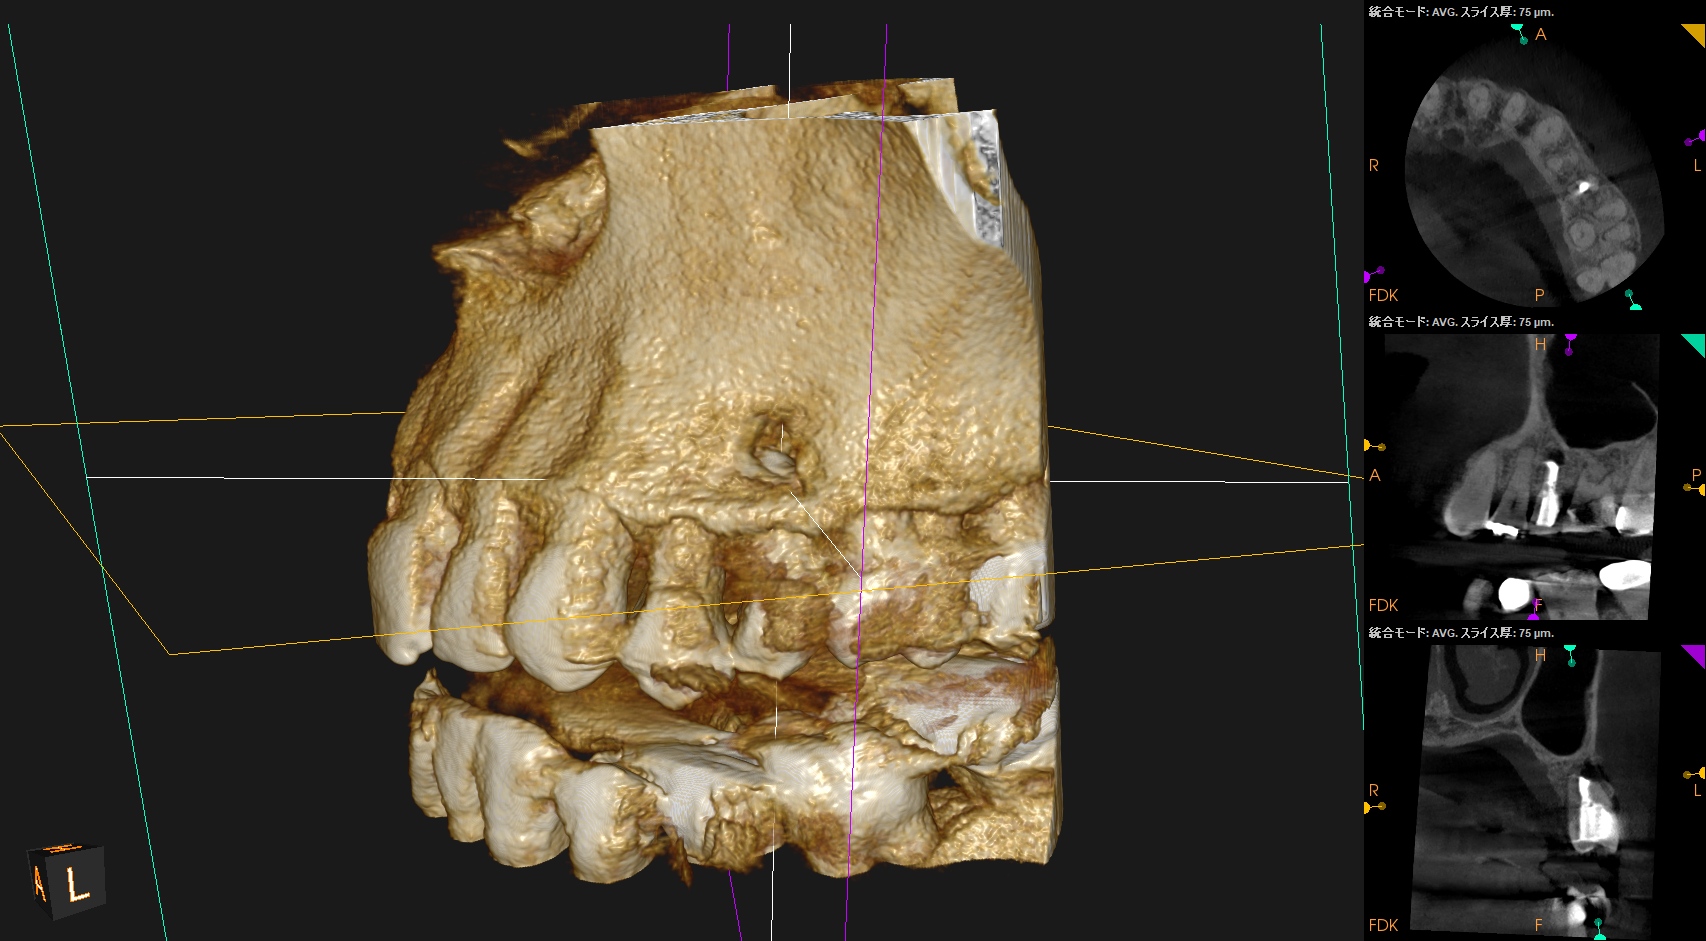

術後にPA, CBCTを撮影した。

再度、何らかの原因で逆根管充填材が外れないように深く逆根管充填した。